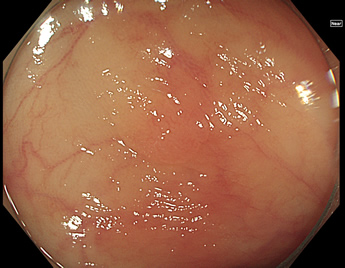

TXIは、「画像の構造を強調する」技術です。これは特別に目新しいものではありません。パソコンの画像編集ソフトや、スマホのアプリでも御馴染みの技術です。しかし、「どのような構造強調が実際に、内視鏡に一番、合うか?(強すぎると不自然になる!)」は、難しい(アナログ的な)課題です。オリンパス社は数タイプのTXIモードを用意しました。半年間の試行錯誤の末、今では下記のモードがベストと判断しました。そして今では「TXI無しの内視鏡は不要(フルタイムTXI)」というまで常用しています。

以下に実例を挙げます

写真だけ、見ると「言われてみるとTXIの方が認識しやすい。でも僅かの差」と感じるでしょうが、この「僅かの差」が、人間の脳での検出には大きな差になります。青い色素(インジゴ・カルミン)が非常に強調され、粘膜の凸凹が明瞭になるのが特徴です。

通常観察 TXIモード